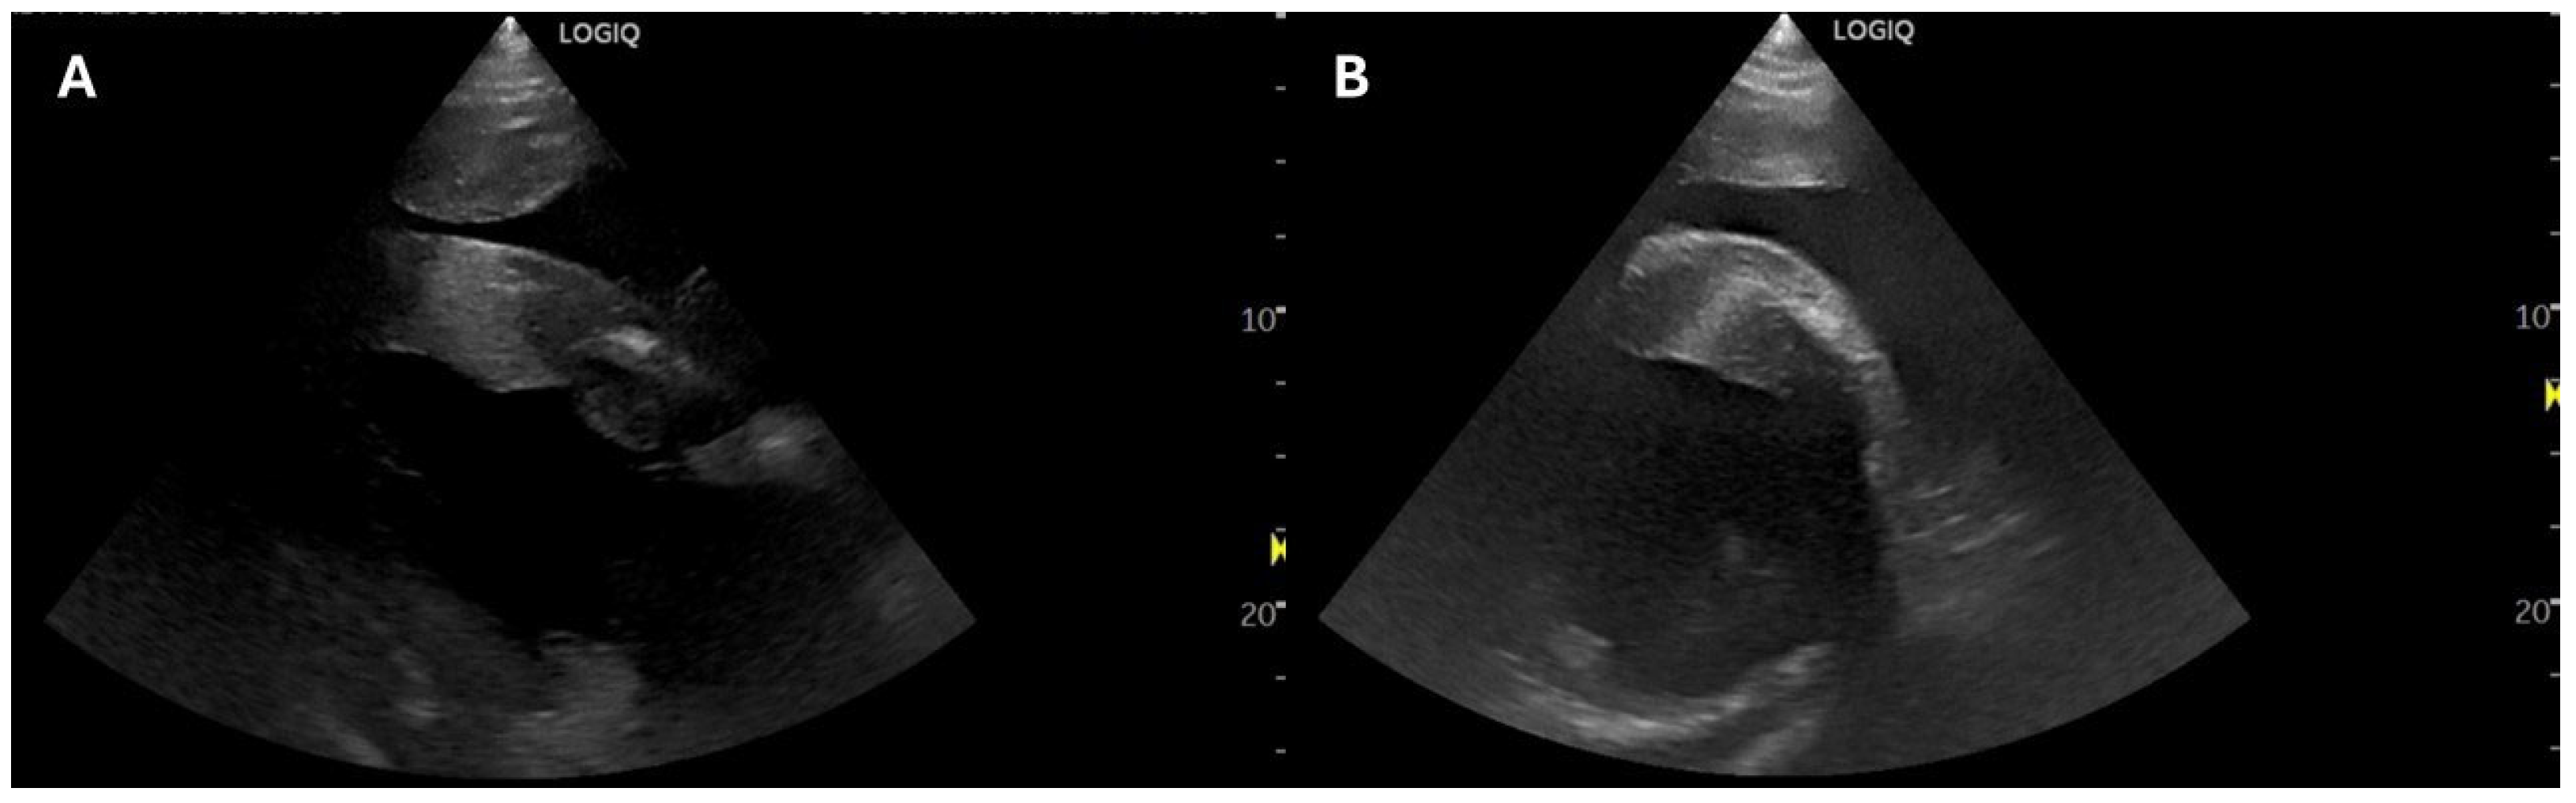

2.1. Case 1

2.2. Case 2

2.3. Case 3